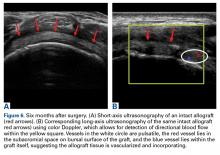

Two weeks to 2 months after surgery, all patients had an intact capsular graft and no pulsatile vessels on US. Between 4 months and 10 months, US showed the construct intact laterally in all cases, a pulsatile vessel in the graft at the tuberosity (evidence of blood flow) in 4 of 5 cases, and a pulsatile vessel hypertrophied in 2 cases ( Figures 6A, 6B ).

After 1 year, all pulsatile vessels were gone. Between 25 months and 36 months, 5 patients had an intact graft construct. Two patients were in motor vehicle accidents during the postoperative period. One had an intact graft laterally, and the other had a ruptured midsubstance. In both cases, MRI was ordered.Magnetic Resonance Imaging

Dermal allograft can also incorporate into the body and transform into host tissue. The literature has described musculoskeletal US as an effective diagnostic and interventional tool. 27-31 We used it to evaluate graft size, patency, and viability. As can be seen on US, the native rotator cuff does not have any pulsatile vessels and is fed by capillary flow. Dermal allograft has native vasculature built into the tissue. After 4 months to 8 months, presence of pulsatile vessels within the graft at the greater tuberosity indicates clear revascularization and incorporation of the tissue (Figure 6B). Disappearance of pulsatile vessels on US after 1 year indicates transformation to a stabilizing structure analogous to capsule or ligament with capillary flow. US also showed graft hypertrophy after 2 years, supporting a finding of integration and growth.